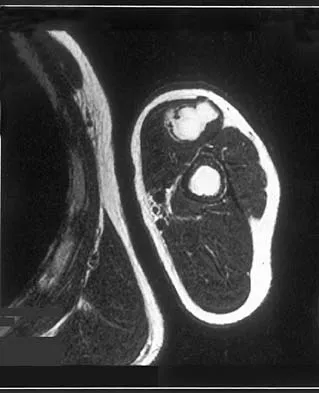

A 35-year-old man reports the development of a painful 2-cm nodule on his dorsal wrist over the past 3 years. A surgeon excised the lesion with a presumptive diagnosis of a ganglion cyst. Histology sections from the excision are shown in Figures 11a and 11b. What is the most likely diagnosis?

Options:

- Ganglion cyst

- Clear cell sarcoma

- Epithelioid sarcoma

- Epidermal inclusion cyst

- Synovial sarcoma

Correct Answer: Clear cell sarcoma

Explanation:

The histologic appearance of the soft-tissue lesion reveals compact nests of cells with a clear cytoplasm surrounded by a delicate border of fibrocollagenous tissue. There can be scattered multinucleated giant cells. This is consistent with a clear cell sarcoma, also called malignant melanoma of soft parts. This tumor is usually positive for S-100 and HMB45 (a melanoma-associated antigen). These tumors are frequently found around the foot and ankle. Similar to epithelioid sarcoma, it is usually intimately bound to tendons or tendon sheaths. Often the tumors are present for many years. The classic histologic appearance of this lesion differentiates it from the other choices. Enzinger FM, Weiss SW: Soft Tissue Tumors, ed 3. St Louis, MO, Mosby, 1995, p 913.

References:

Lucas DR, Nascimento AG, Sim FH: Clear cell sarcoma of soft tissues: Mayo Clinic experience with 35 cases. Am J Surg Pathol 1992;16:1197-1204.